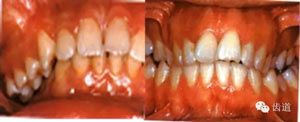

2)、上下前牙間的覆蓋關(guān)系:有否深覆蓋或反覆蓋

A、覆蓋:自上前牙切端到下前牙唇面的最大水平距離。

78.jpg

B、深覆蓋:上下前牙切端的前后距離超過(guò)3mm以上者。分為3度。

79.jpg

C、反覆蓋:下前牙切端位于上前牙切端之唇側(cè)。

80.jpg

81.jpg

前 牙 覆 蓋

l正常覆蓋:上下切牙切端的前后距離不大于3mm.

lⅠ度深覆蓋:上下切牙切端的前后距離3-5mm.

lⅡ度深覆蓋:上下切牙切端的前后距離5-8mm.

lⅢ度深覆蓋:上下切牙切端的前后距離大于8mm.